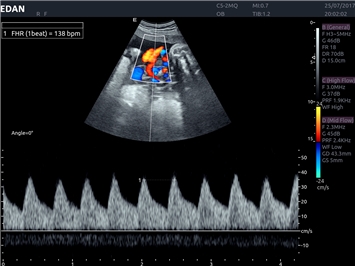

EDAN Acclarix LX4 представляет собой инновационную ультразвуковую систему, построенную на усовершенствованной платформе Acclarix. Сочетание высокого качества визуализации с интеллектуальным рабочим процессом делает эту систему оптимальным выбором для клиник, ценящих эффективность и экономичность.

Инновационные функции обработки изображений:

• Функция eSRI для подавления зернистости изображения

• Тканевая допплеровская визуализация (TDI)

Цветовой допплер:

Да

Импульсно-волновой допплер: